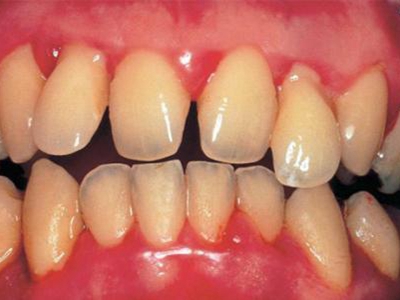

慢性龈炎又称边缘性龈炎或单纯性龈炎,主要表现为游离龈和龈乳头因炎性水肿,而变为鲜红或暗红色,龈缘变厚,龈乳头圆钝肥大。慢性龈炎的患病率高,治愈后仍可复发,部分患者可发展成为牙周炎。

慢性龈炎的病损部位一般局限于游离龈和龈乳头,以前牙区为主,尤其以下前牙区最为显著,患者常因刷牙或咬硬物时牙龈出血而就诊。游离龈和龈乳头颜色变为鲜红或暗红色,病变较重时炎性充血可波及附着龈。龈缘变厚,龈乳头圆钝肥大,可增生呈球状,覆盖牙面。牙龈松软脆弱,缺乏弹性。

当牙龈以增生性反应为主时,龈缘和龈乳头呈坚韧的实质性肥大,质地较硬而有弹性。龈沟液量增多,还可能出现龈沟溢脓现象。